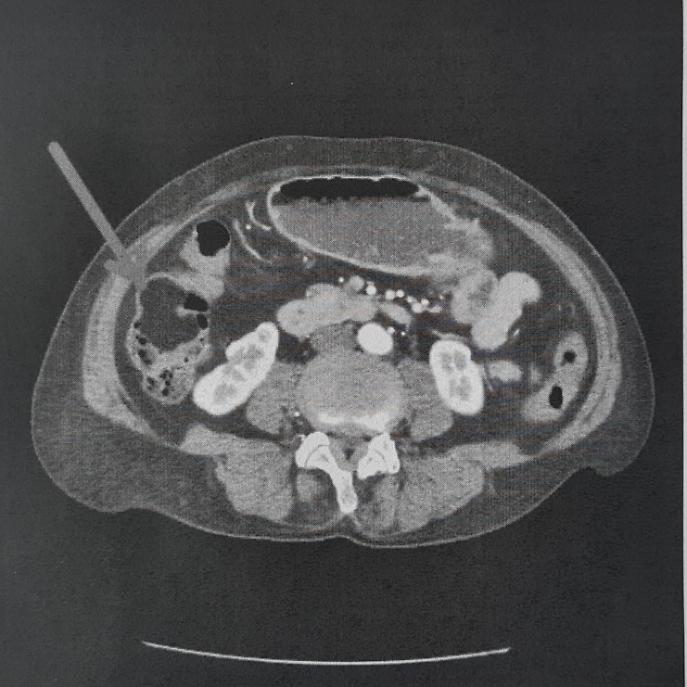

Gli esami diagnostici, tra cui una Tac addome, hanno mostrato una subocclusione intestinale provocata da una massa di oltre 6 cm, sviluppata nella parete del colon destro. La conferma è arrivata con la colonscopia, che ha certificato la necessità di un intervento immediato. Dopo una valutazione anestesiologica, la donna è stata sottoposta a emicolectomia destra laparoscopica, procedura mini-invasiva che ha consentito la rimozione del tumore e una più rapida ripresa postoperatoria.

Il decorso clinico è stato seguito in collaborazione con cardiologi e internisti del presidio, con dimissione dopo 10 giorni. L’analisi istologica eseguita dall’Istituto Oncologico di Bari ha diagnosticato un lipoma sottomucoso maturo, un tumore benigno raro. “Si tratta di una evenienza poco frequente – sottolinea il dr. Cianci –. Queste formazioni rappresentano tra lo 0,035% e il 4,4% delle neoplasie benigne non epiteliali del tratto gastrointestinale e diventano sintomatiche solo quando raggiungono dimensioni importanti. La laparoscopia ha ridotto tempi di recupero e complicanze”.